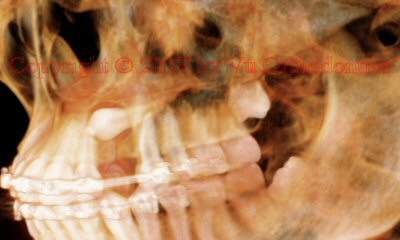

Example 1: Impacted canine, upper left

Fig. 4 An image of the CBCT scan, showing horizontally impacted upper left canine